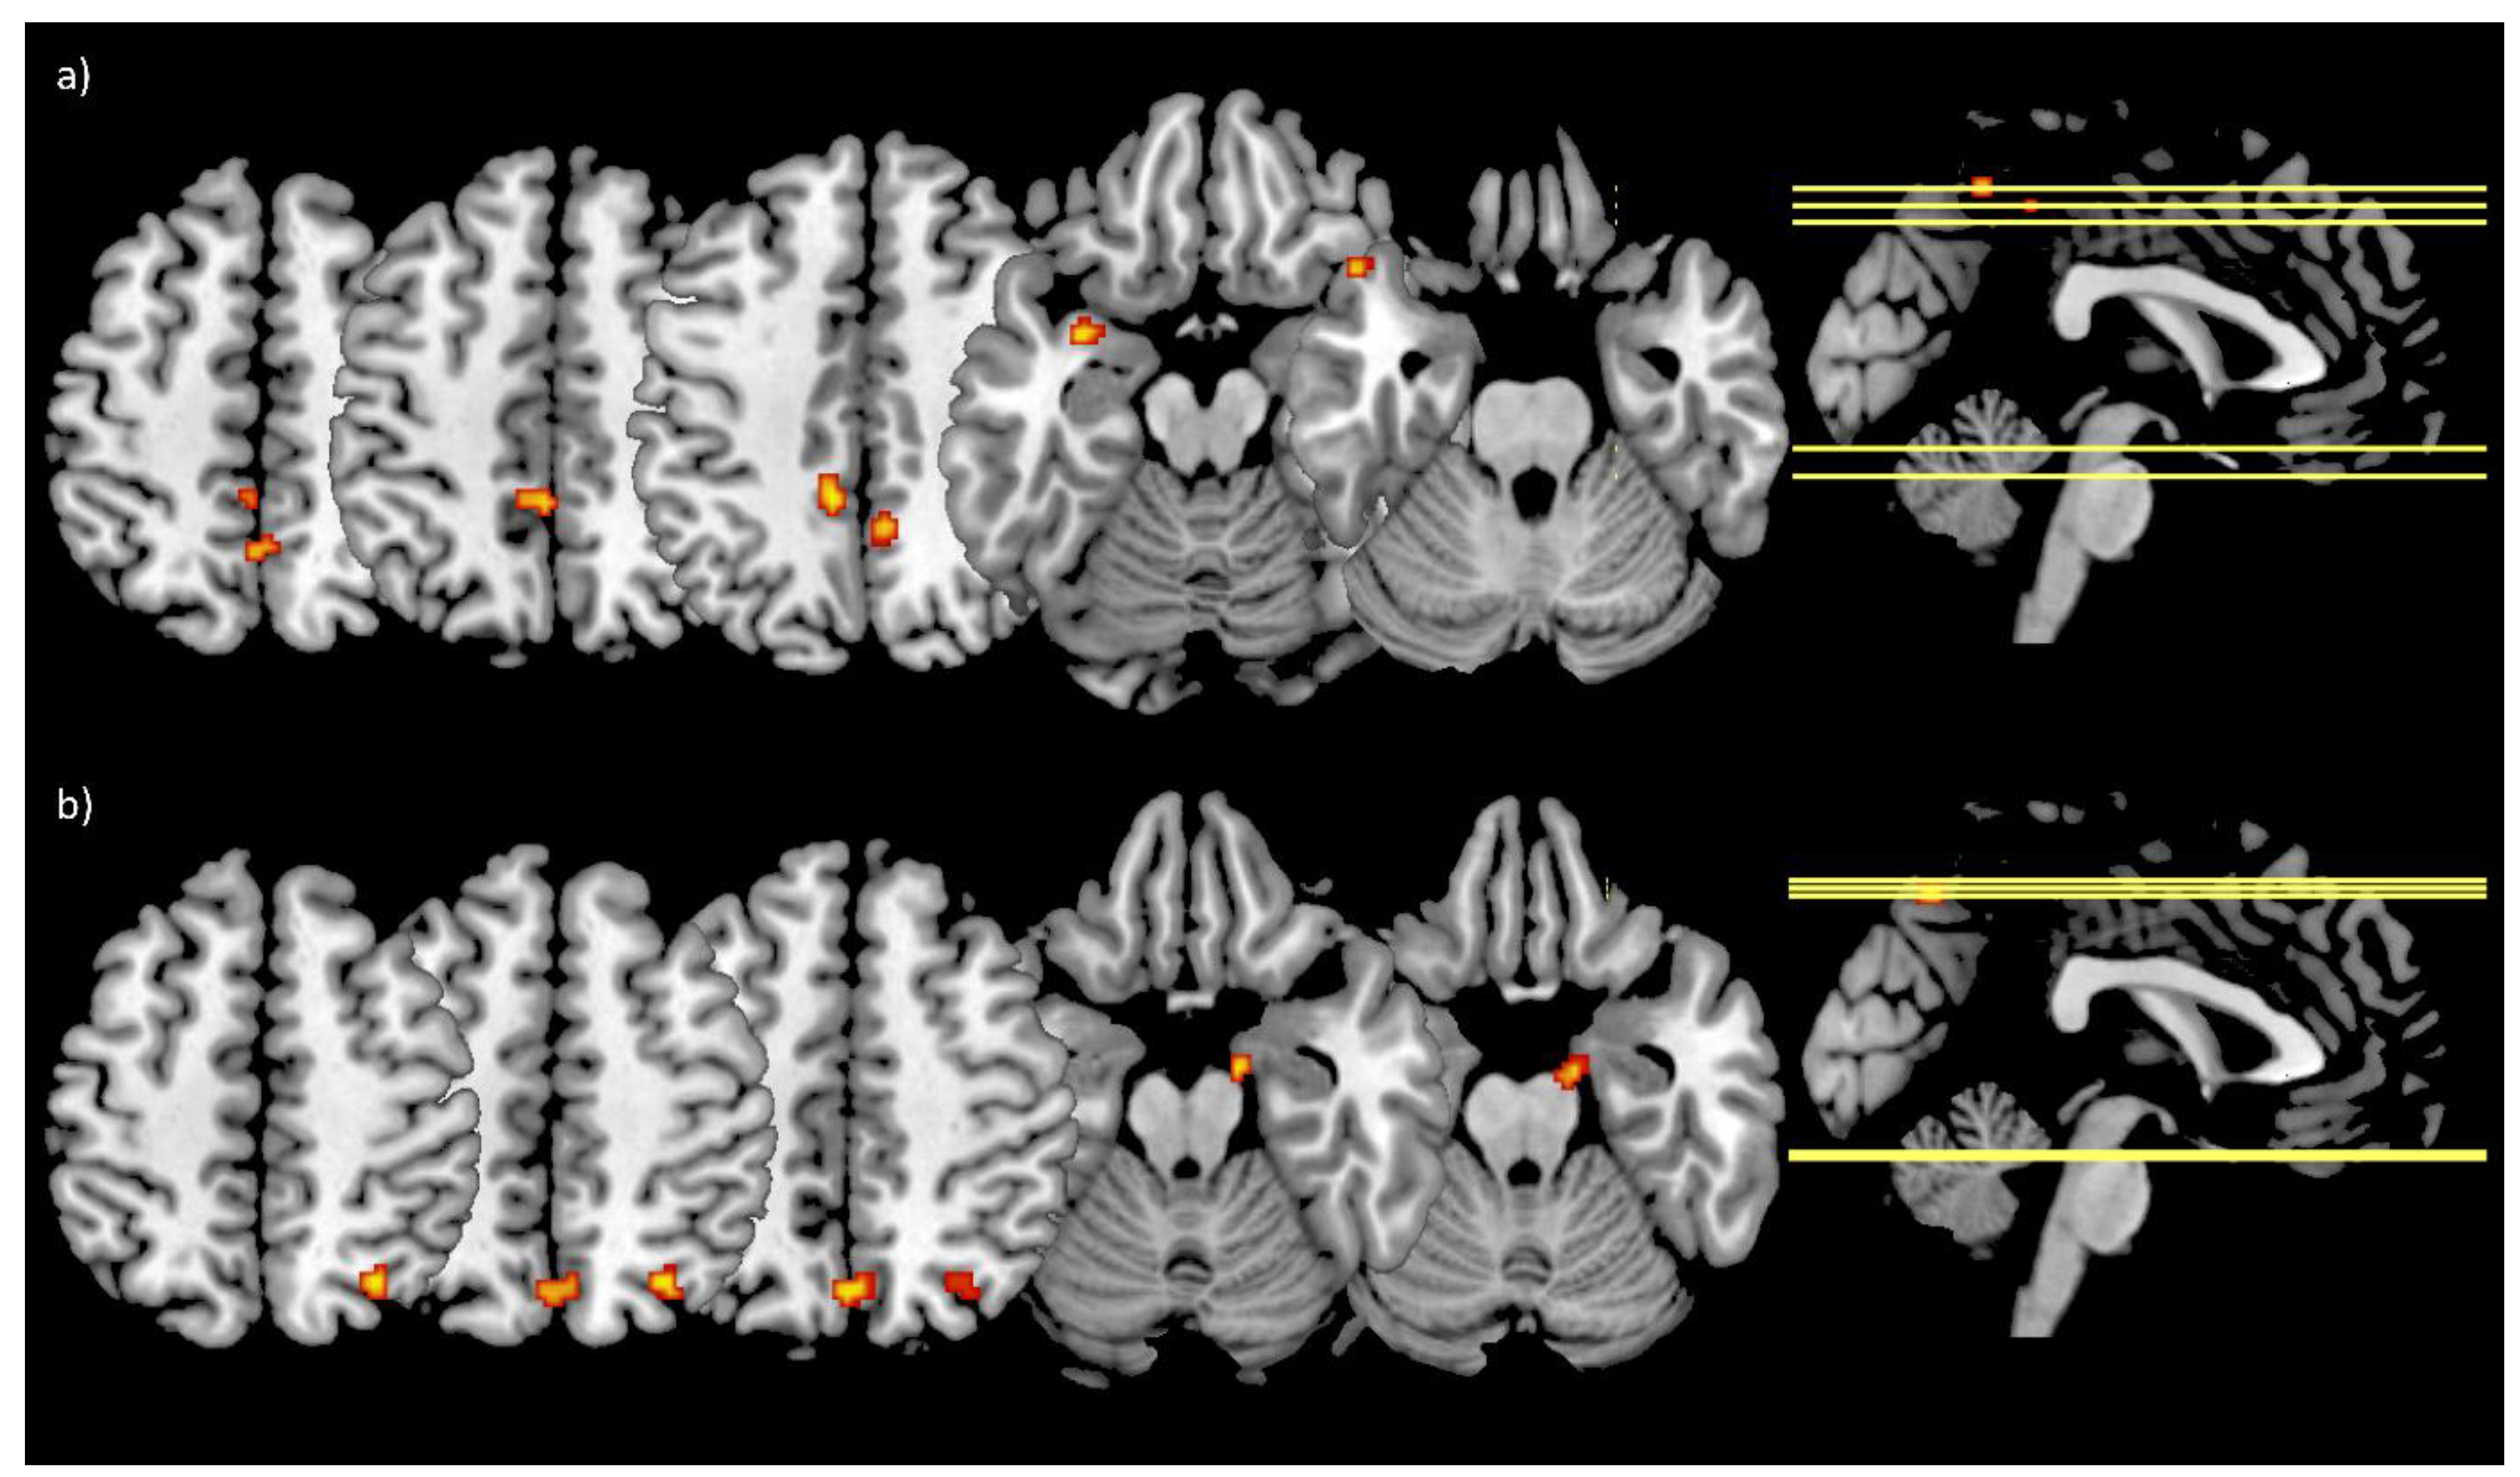

3.5. Functional Connectivity

3.6. Correlation Analyses